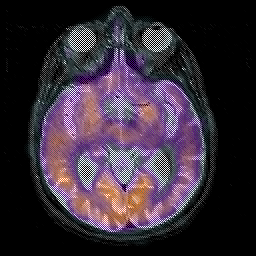

Alzheimer's disease, overlay -- Slice #21

[Home][Help][Clinical][Tour 1][Tour 2] Slice 21